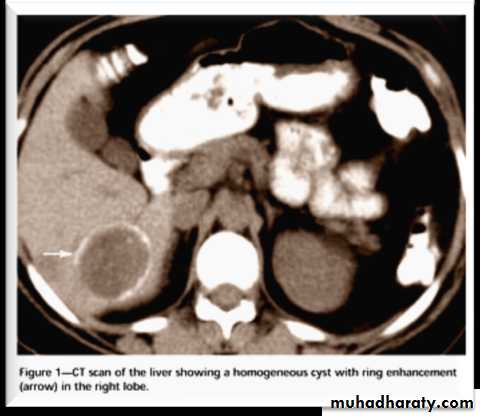

• Echinococcus granulosus: Diagnosis

• Endemicity• Symptoms

• X-ray and CT scan

• Serology

• Skin (Casoni) test